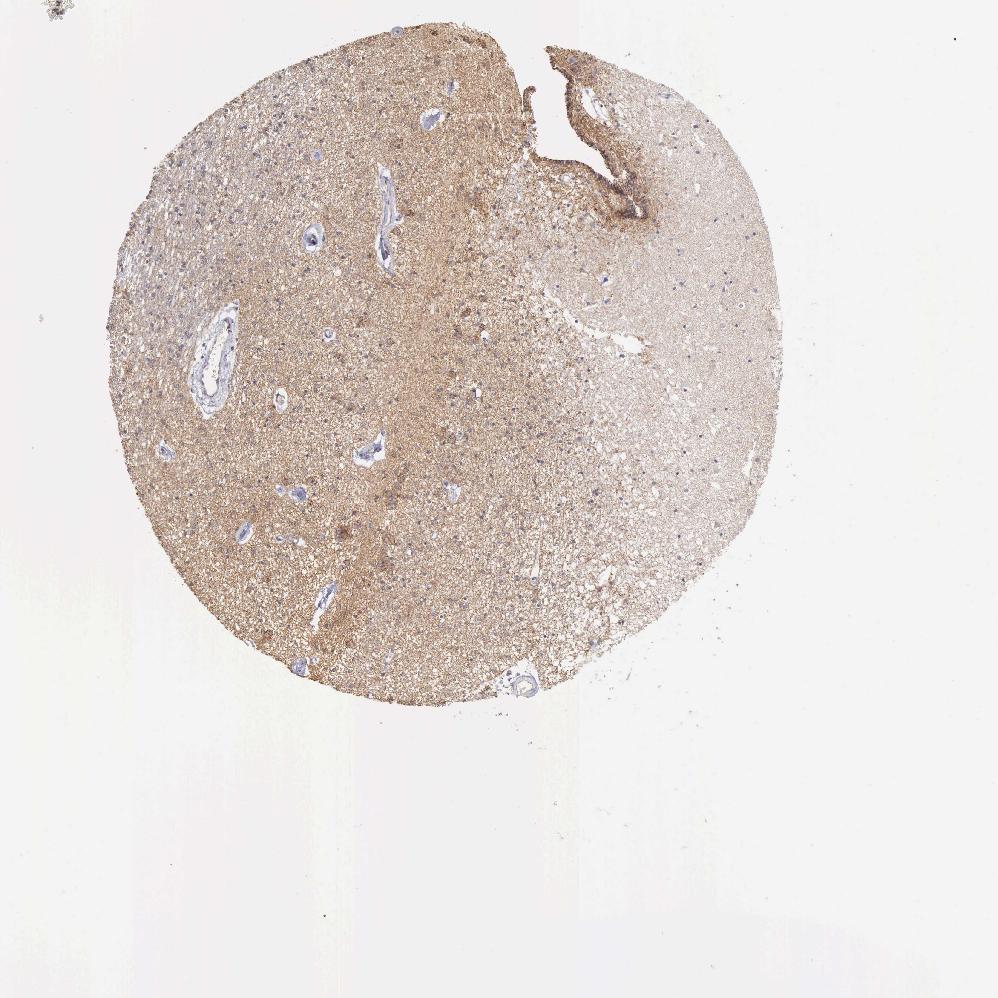

CAUDATE - Antibody stainingi

Antibody staining in the annotated cell types in the current human tissue is reported as not detected, low, medium, or high, based on conventional immunohistochemistry profiling in selected tissues. This score is based on the combination of the staining intensity and fraction of stained cells.

Each image is clickable and will lead to virtual microscopy that enables deeper exploration of all samples and also displays staining intensity scores, fraction scores and subcellular localization as well as patient and tissue information for each sample.

Antibody HPA001066

Glial cells Medium

Neuronal cells Medium